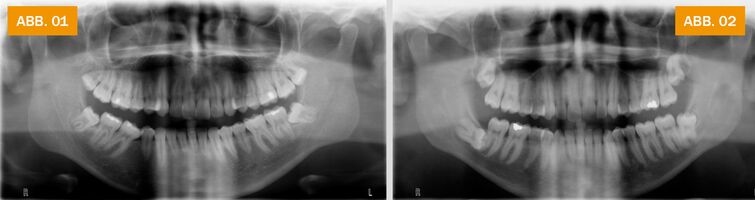

ABB.02: Röntgenbild mit „Retiniertem Weisheitszahn“ im rechten Unterkiefer (auf dem Bild links): der Zahn liegt quer, vollständig unter der Schleimhaut und drückt auf den davor liegenden zweiten Backenzahn